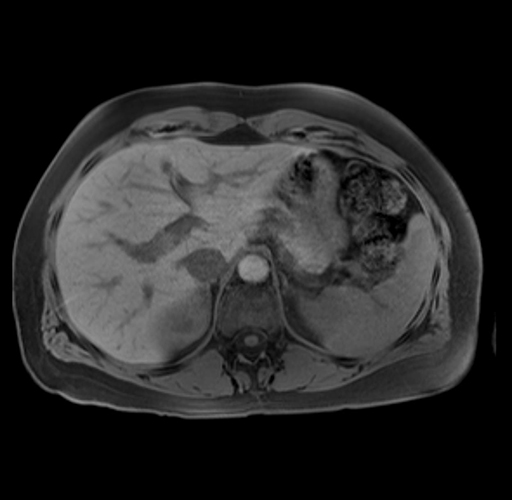

Imaging Analysis

Look through the patient's CT scan to identify any areas of concern for the necessary procedure.

Based on your CT findings, which issue(s) are present and would give reason for "planned slowing down moment(s)" in this case?

Considering a standard distal pancreatectomy procedure, what step(s) of the operation would you do differently in this case?